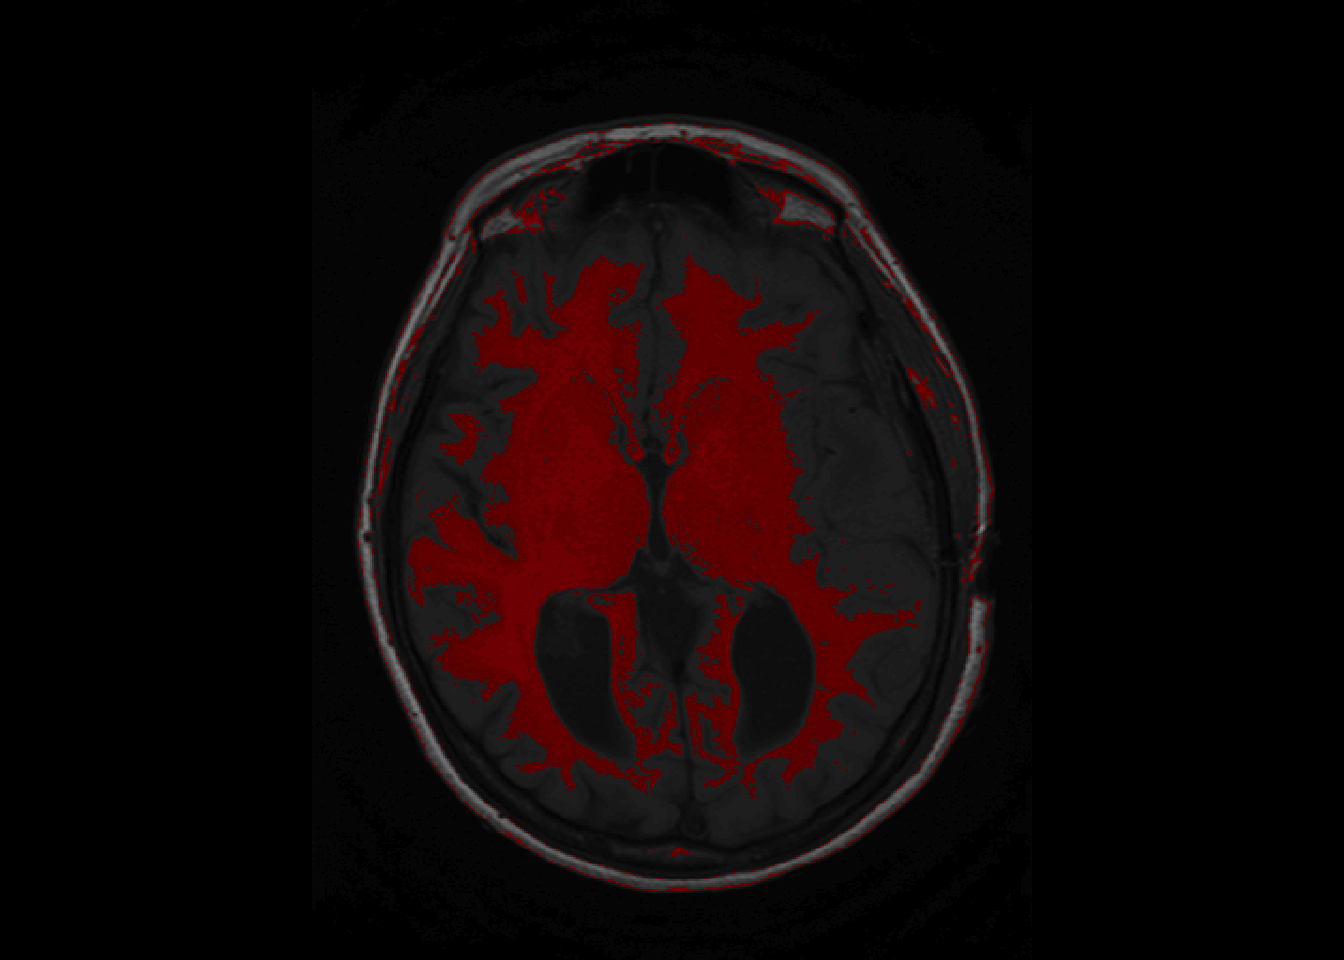

Backmapping consists of overlaying a mask over an image of the brain. A basic backmapping can be achieved by taking creating a mask according to intensities and calling the function overlay.

is_btw_300_400 = nii_T1 > 300 & nii_T1 < 400

nii_T1_mask = nii_T1

nii_T1_mask[!is_btw_300_400] = NA

overlay(nii_T1, nii_T1_mask, z = 11, plot.type="single")

overlay can be called to show a single slice as above, or the whole brain as below.